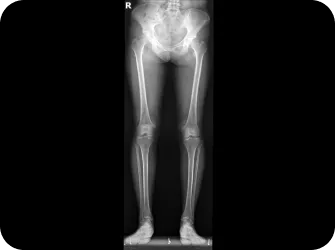

예를 들어, 다리 길이의 차이, 골반의 불균형, 몸체의 좌우면의 성장의 길이가 다를 때, 근육질환 또는 신경질환으로 척추가 휘는 측만증입니다. 성장기가 지나고 노화기에 근육와 약화로 더 많이 틀어질 수 있으며, 퇴행을 가속화시켜 근골격계 질환의 원인이 되기도 합니다.

다리길이 엑스레이 검사

휜다리 증상 확인